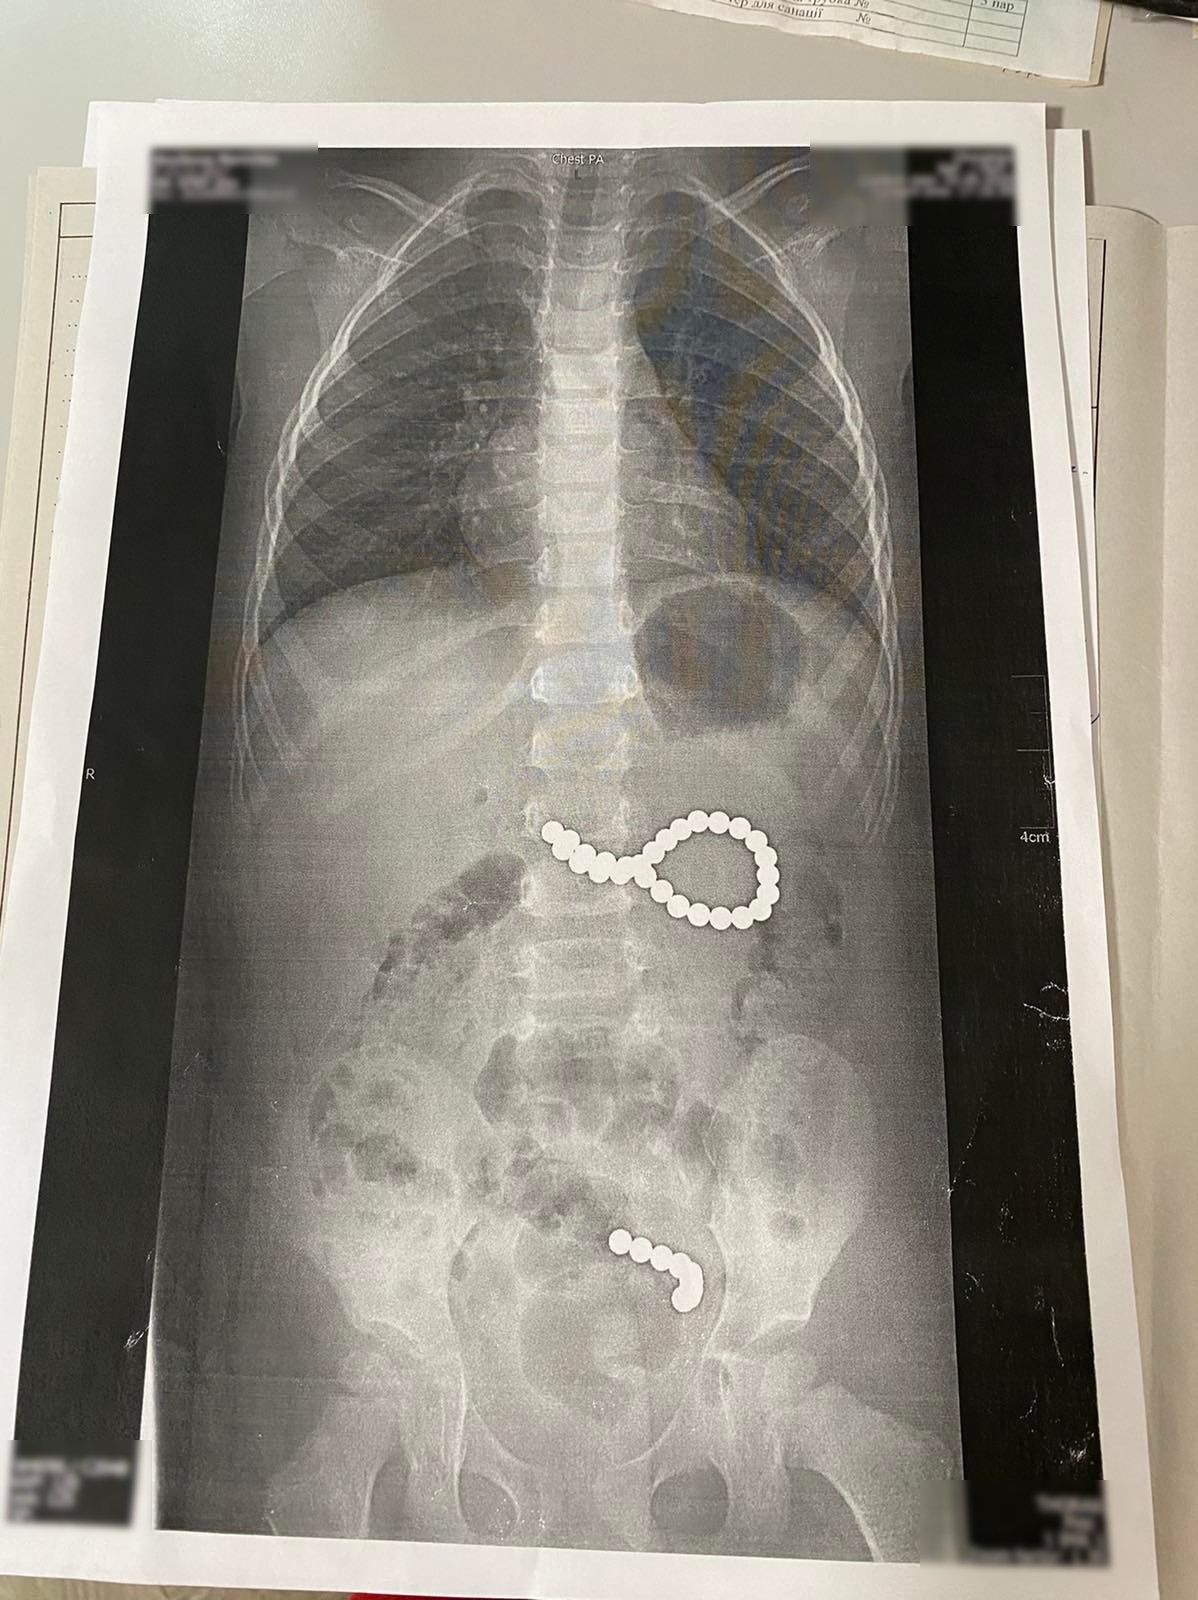

Во Львовской областной детской больнице ОХМАТДЕТ провели срочную операцию трехлетней девочке из Дрогобычского района, которая проглотила 36 магнитных шариков от конструктора. Девять шариков под действием магнитного поля образовали цепочку и попали в кишечник, еще 27 шариков образовали неправильный круг и попасть в кишечник не могли. Девочку пришлось срочно оперировать.

"Девять шариков, которые ребенок проглотил в пятницу, образовали цепочку, потому что было сильное магнитное поле. И они прошли из желудка в тонкий кишечник. А те 27 магнитных шариков, которые ребенок проглотил в субботу, образовали неправильный круг и их срочно надо было доставать. Шарики были диаметром около 4 мм, скорее всего, из какого-то конструктора", - рассказала врач Горбач.

Медики пытались извлечь шарики с помощью эндоскопа под общим наркозом.

"Сначала нам не удавалось. Шарики круглые, они постоянно соскакивали из эндоскопических петель, других приспособлений. Впоследствии мы один за другим извлекли 27 шариков. Девять, попавшие в кишечник, вышли естественным путем", - рассказала хирург.